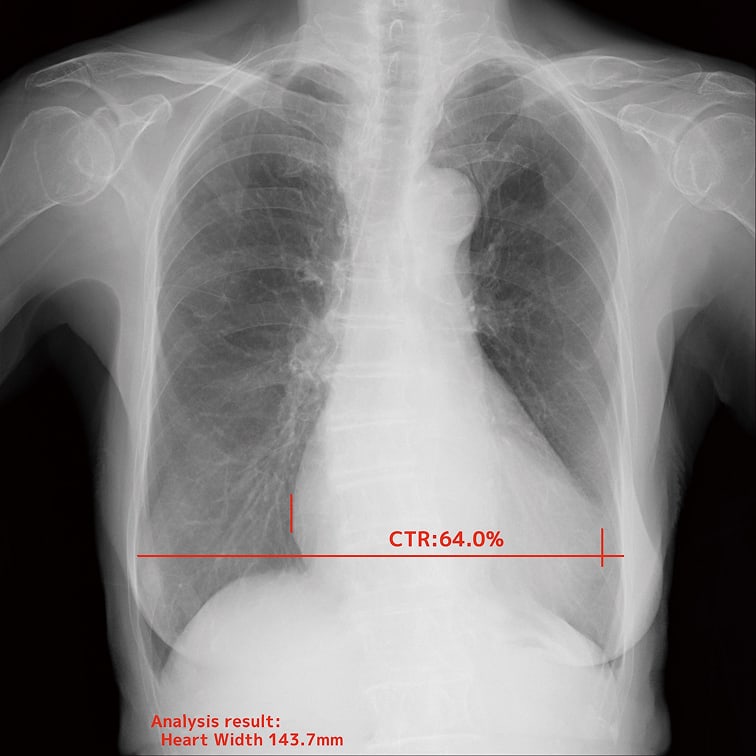

- 心胸郭比

EIRLが胸部X線画像上のランドマークを認識し、自動で計測。計測のばらつきを抑えながら、日常業務の負担を大幅に軽減します。

自動計測機能